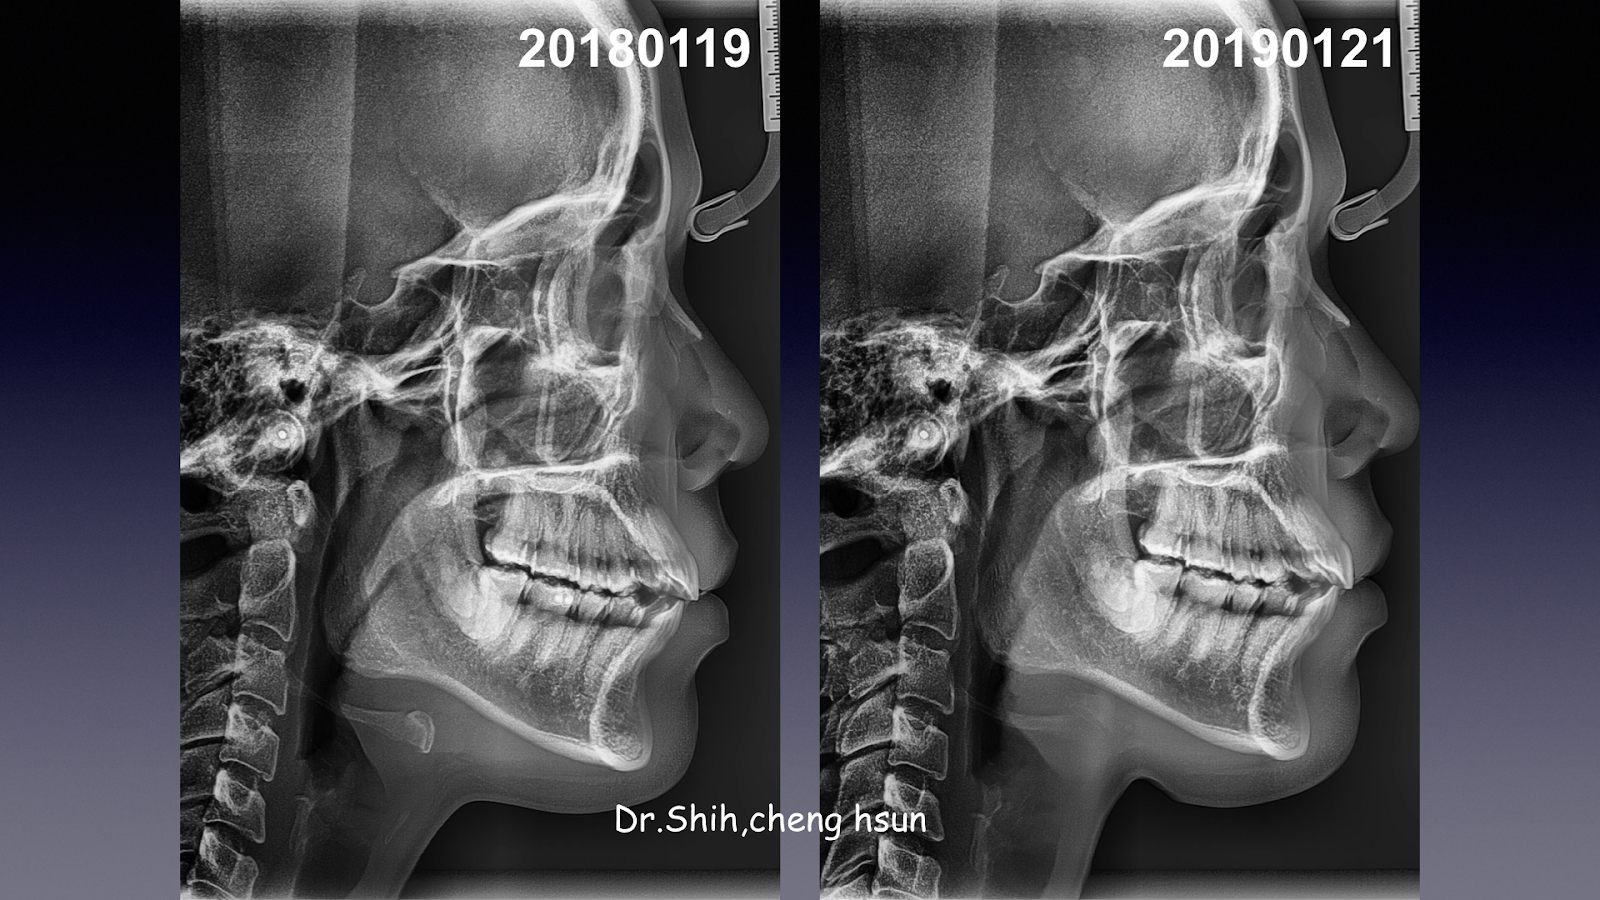

| 術後牙根平行度良好 |